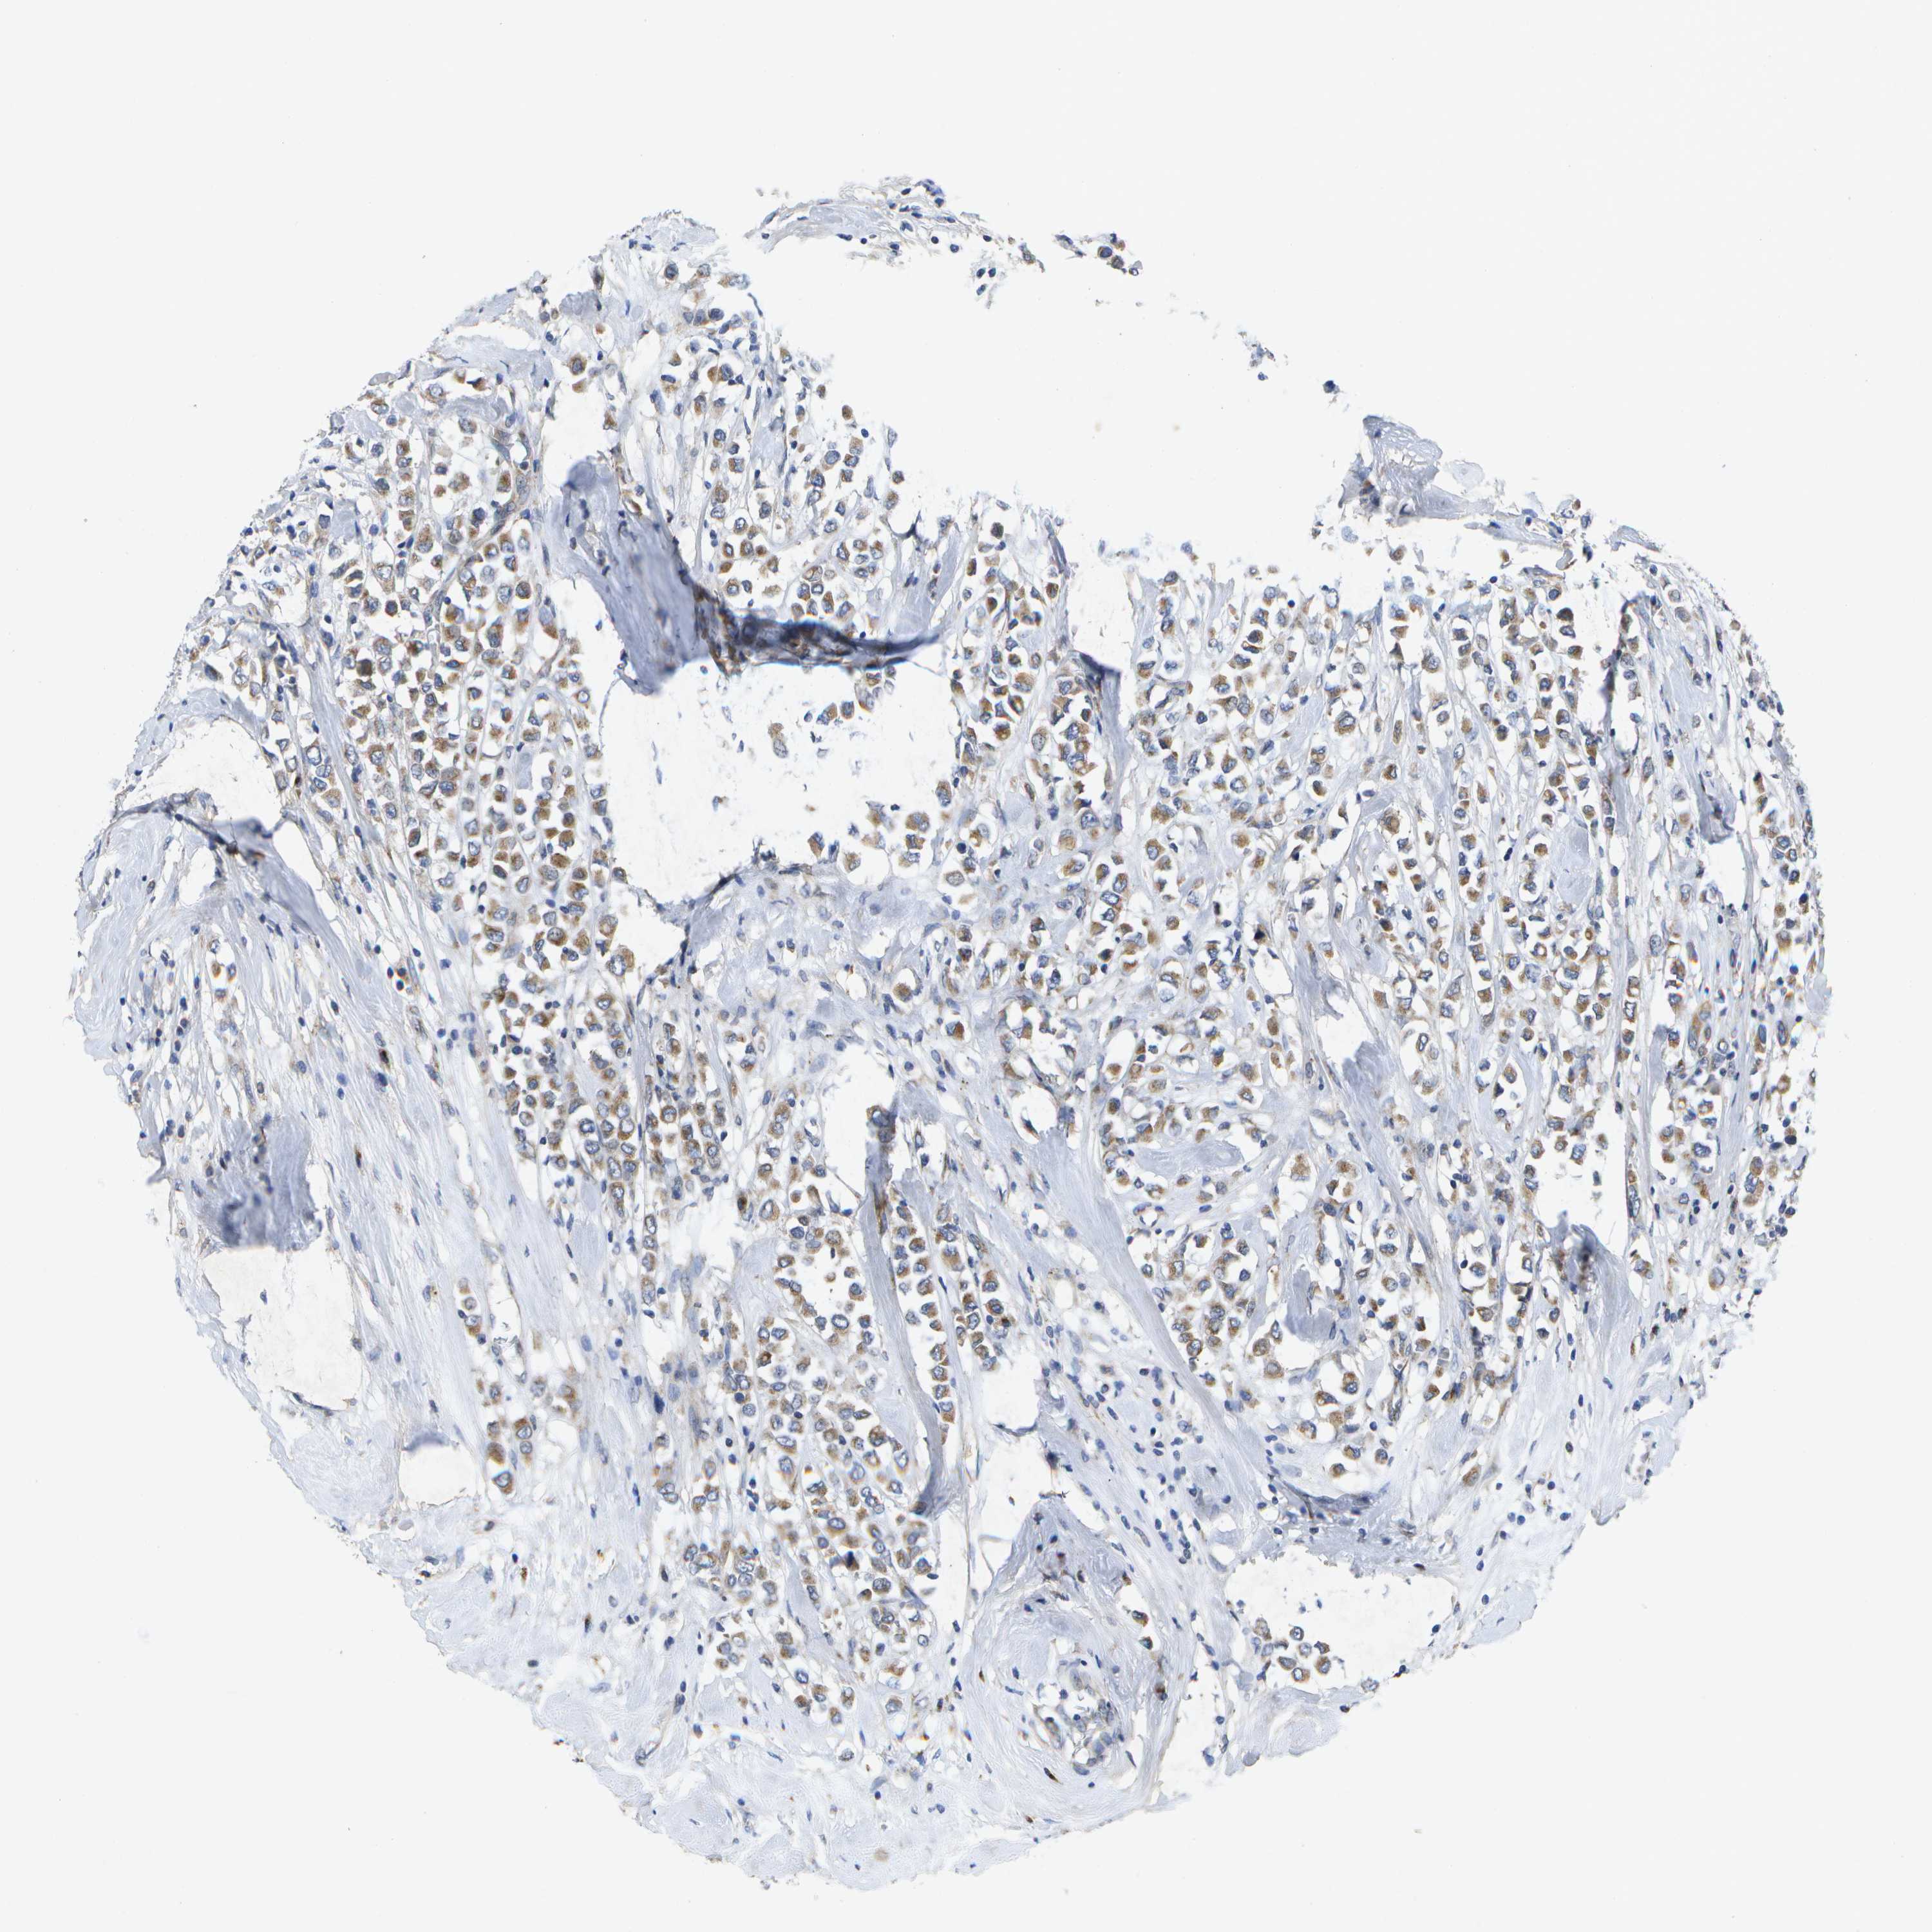

CANCER BREAST CANCER Show tissue menu

BRCA TCGA BRCA VALIDATION PROTEIN EXPRESSION

Breast cancer

Human cancer

KDELR1 is not prognostic in Breast Invasive Carcinoma (TCGA)